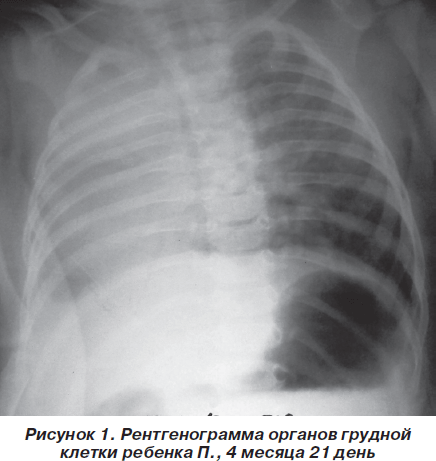

Медицина и диагностика: Аномалии ребер на рентгене